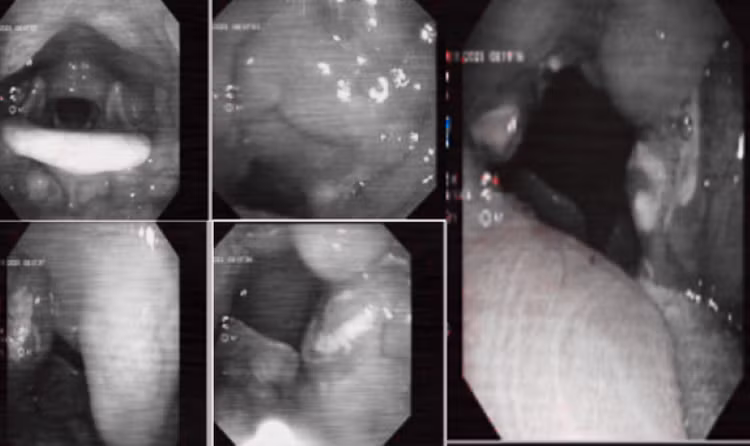

Kết quả nội soi tai mũi họng của bệnh nhân/Ảnh Medlatec

Tại đây, bác sĩ tiến hành thăm khám lâm sàng và chỉ định các kỹ thuật cận lâm sàng cần thiết phục vụ chẩn đoán. Khám tai mũi họng cho thấy tình trạng môi khô, lưỡi bẩn, hơi thở hôi, sốt cao nhất 38,9 độ, sưng tấy vùng dưới hàm.

Kết quả nội soi tai mũi họng phát hiện niêm mạc họng nề đỏ, amidan hai bên quá phát có nhiều giả mạc mủ. Chẩn đoán xác định, bệnh nhân mắc viêm amidan cấp mủ. Bác sĩ chỉ định phác đồ điều trị bằng kháng sinh, giảm viêm, giảm đau tại chỗ.